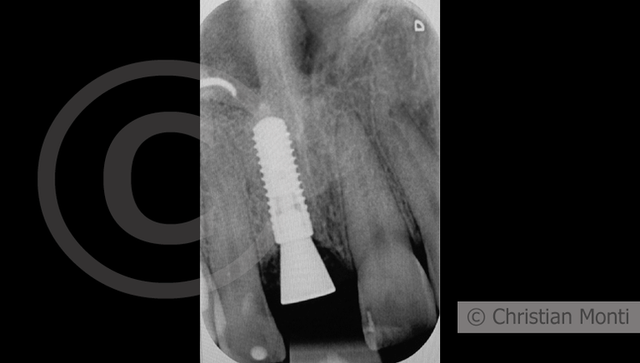

EDENTULIA SINGOLA

Impianto in sostituzione di un incisivo superiore